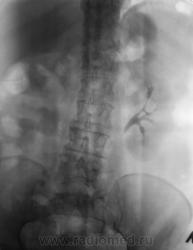

Пациент направлен на внутривенную урографию. Диагноз - "Мочекаменная болезнь?". Врач УЗИ сообщил, что "камни" с обеих сторон. По поводу картины сильно не распространялся.

1. Пациент? Или пациентка? (судя по ширине малого таза и наличия в нем обызествления характерного в большей степени для обызествленного фиброматозного узла);

2.Крупный коралл правой почки и камень лоханки левой почки;

3.Блок правой почки, как следствие МКБ (камни в средней трети правого мочеточника);

4. Отток слева не нарушен;

5.Округлый дефект выполнения в области устья правого мочеточника вполне может быть обьяснен наличием уретероцеле, а тогда станет понятна и причина камнеобразования справа.

Пациентка, наша коллега, врач.

Фрагмент с мочевым пузырем.

Пациентку сегодня прооперировали в областной больнице. Со слов начмеда знаю только одно - удалили почку.

Сегодня говорил с коллегой - пациентной.

Да, камень в мочеточнике, гидронефроз, почка удалена.

В мочевом пузыре - доброкачественная опухоль.